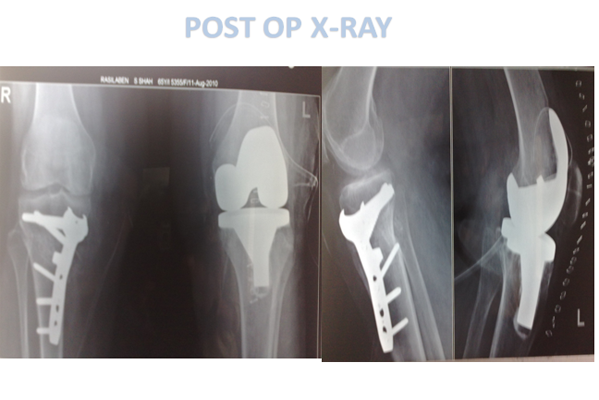

HTO

Rashilaben